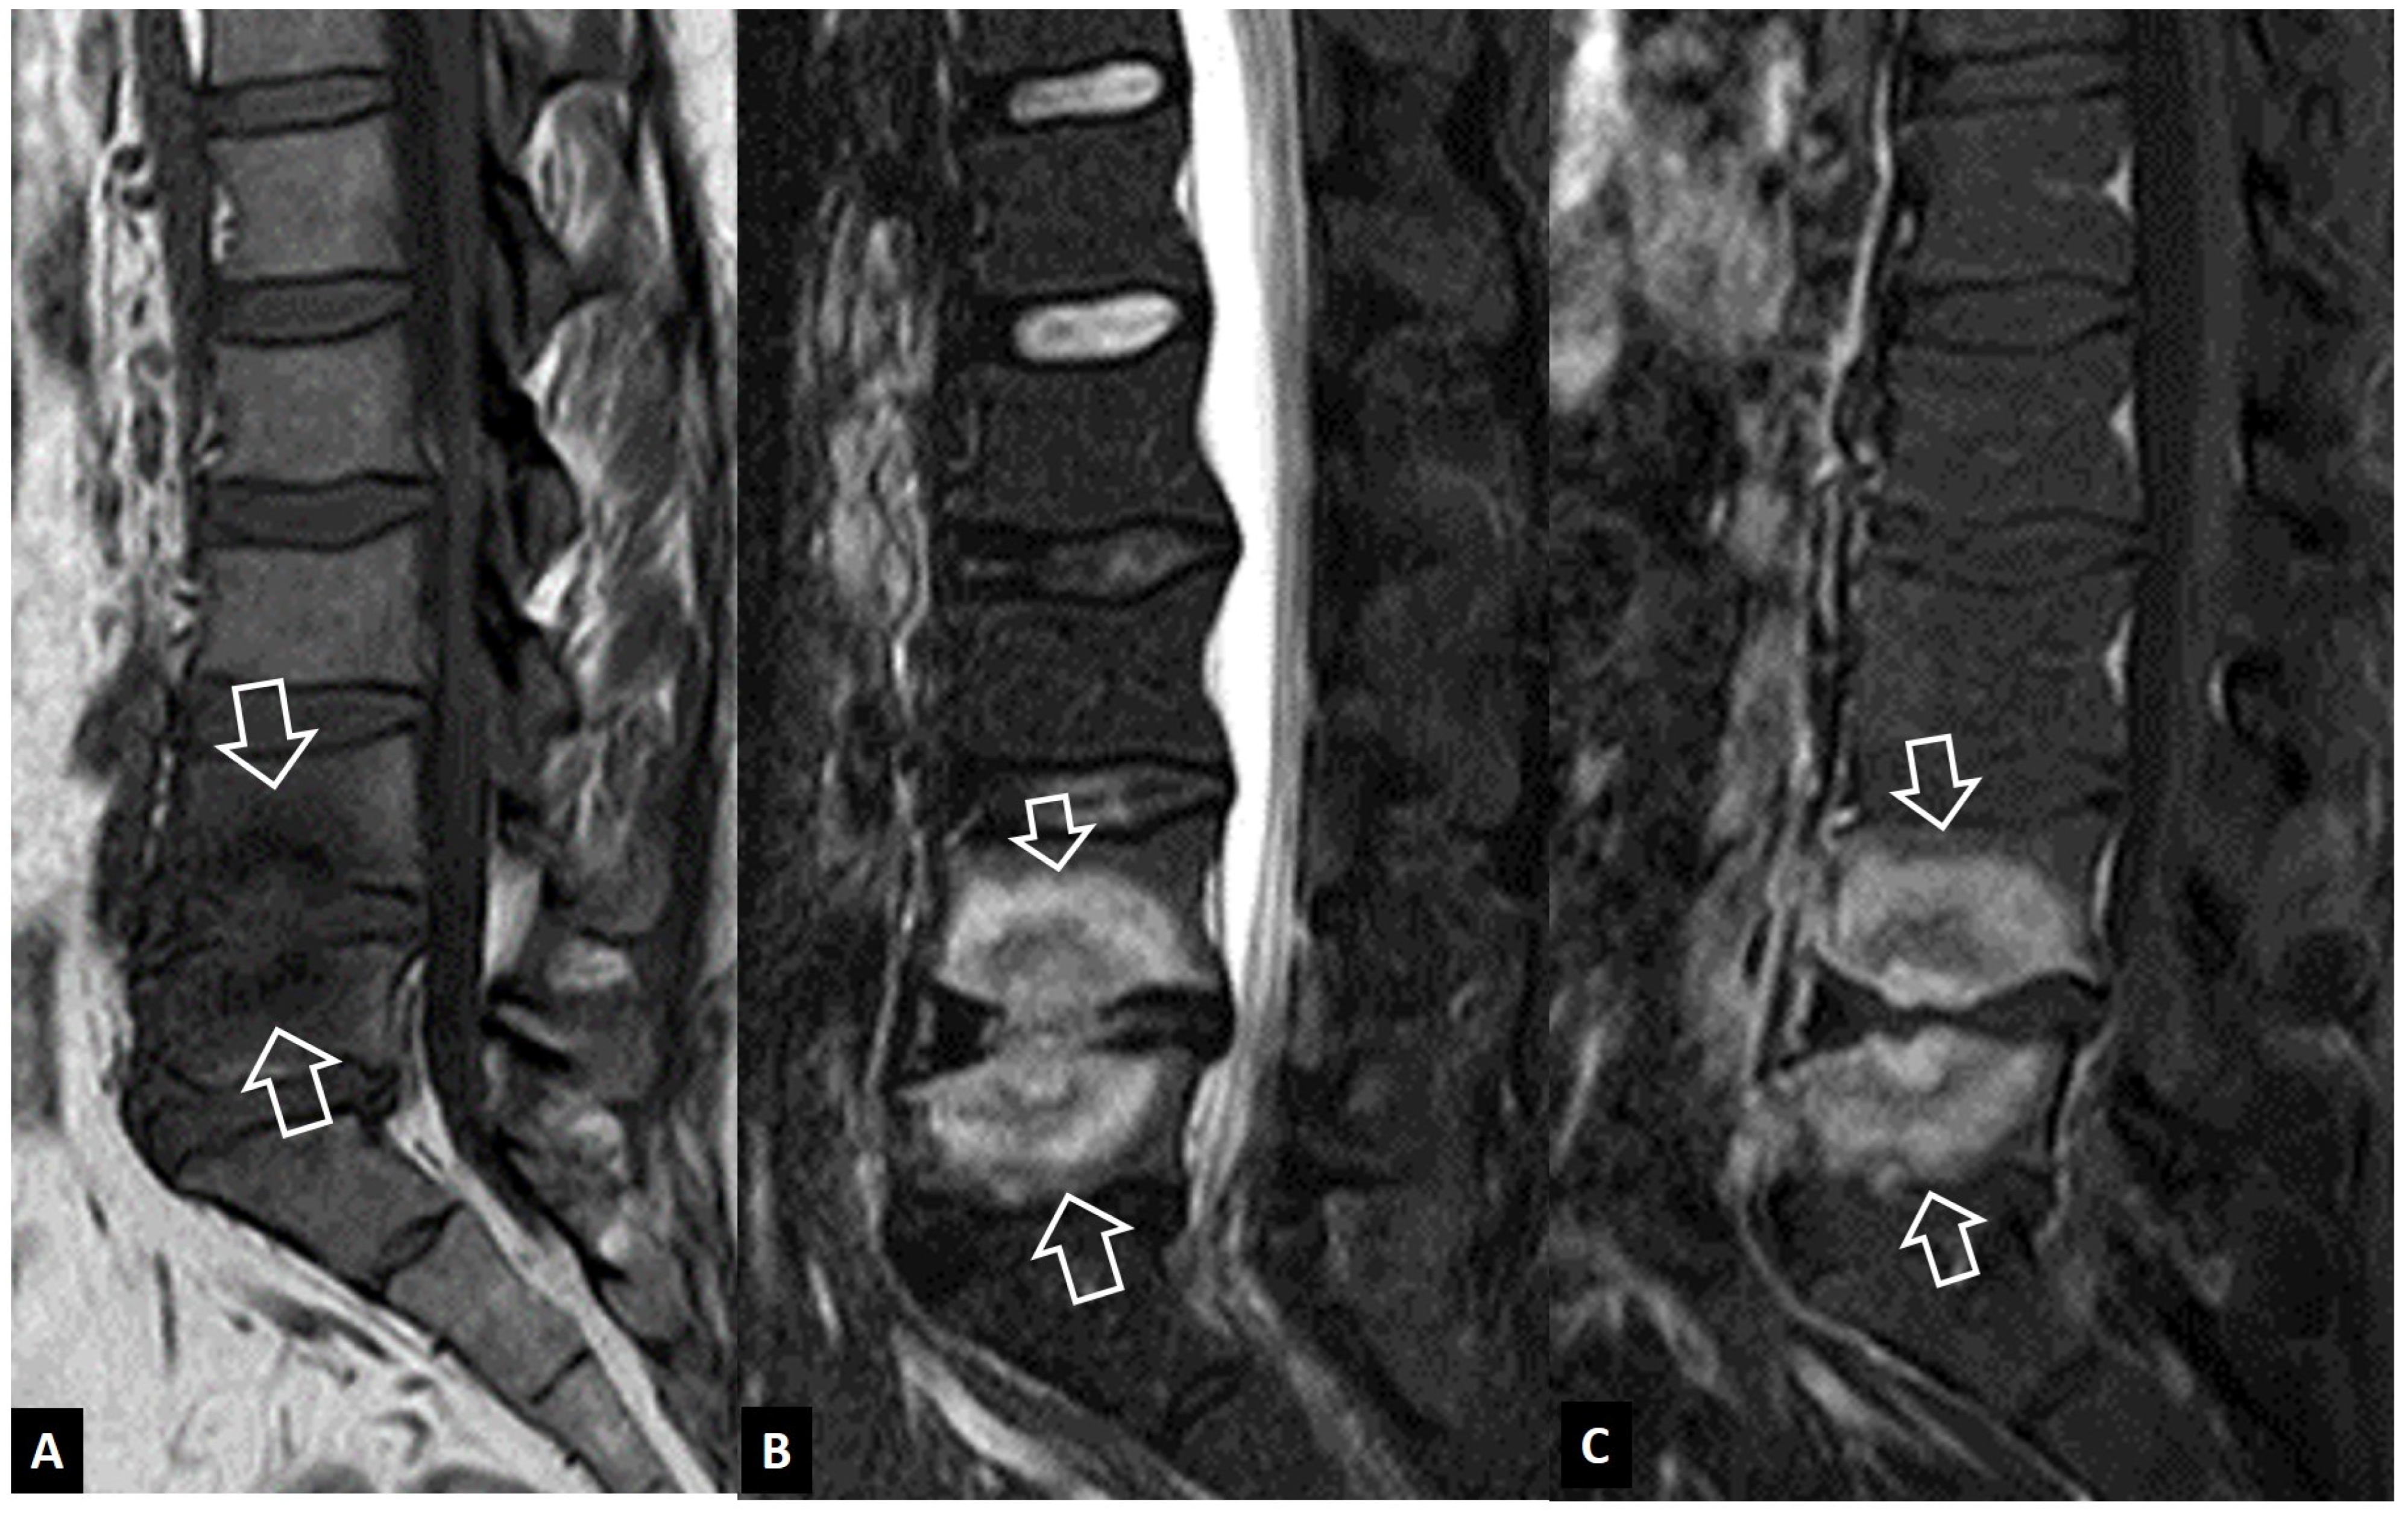

2.1.3. SAPHO Syndrome

2.1.4. Destructive Spondyloarthropathy

2.2. Non-Infectious Sacroiliitis